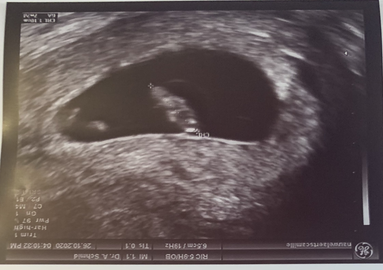

Tijdens al deze controles liet ik ook niet altijd graag zien. Ach jah, zo een echo... wie kan daar nu eigenlijk iets uit opmaken. πŸ˜‚